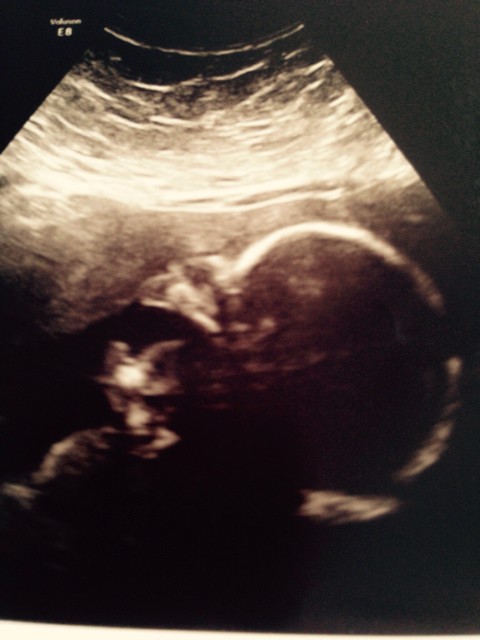

madzia -świetny nosek!!! taki malutki )